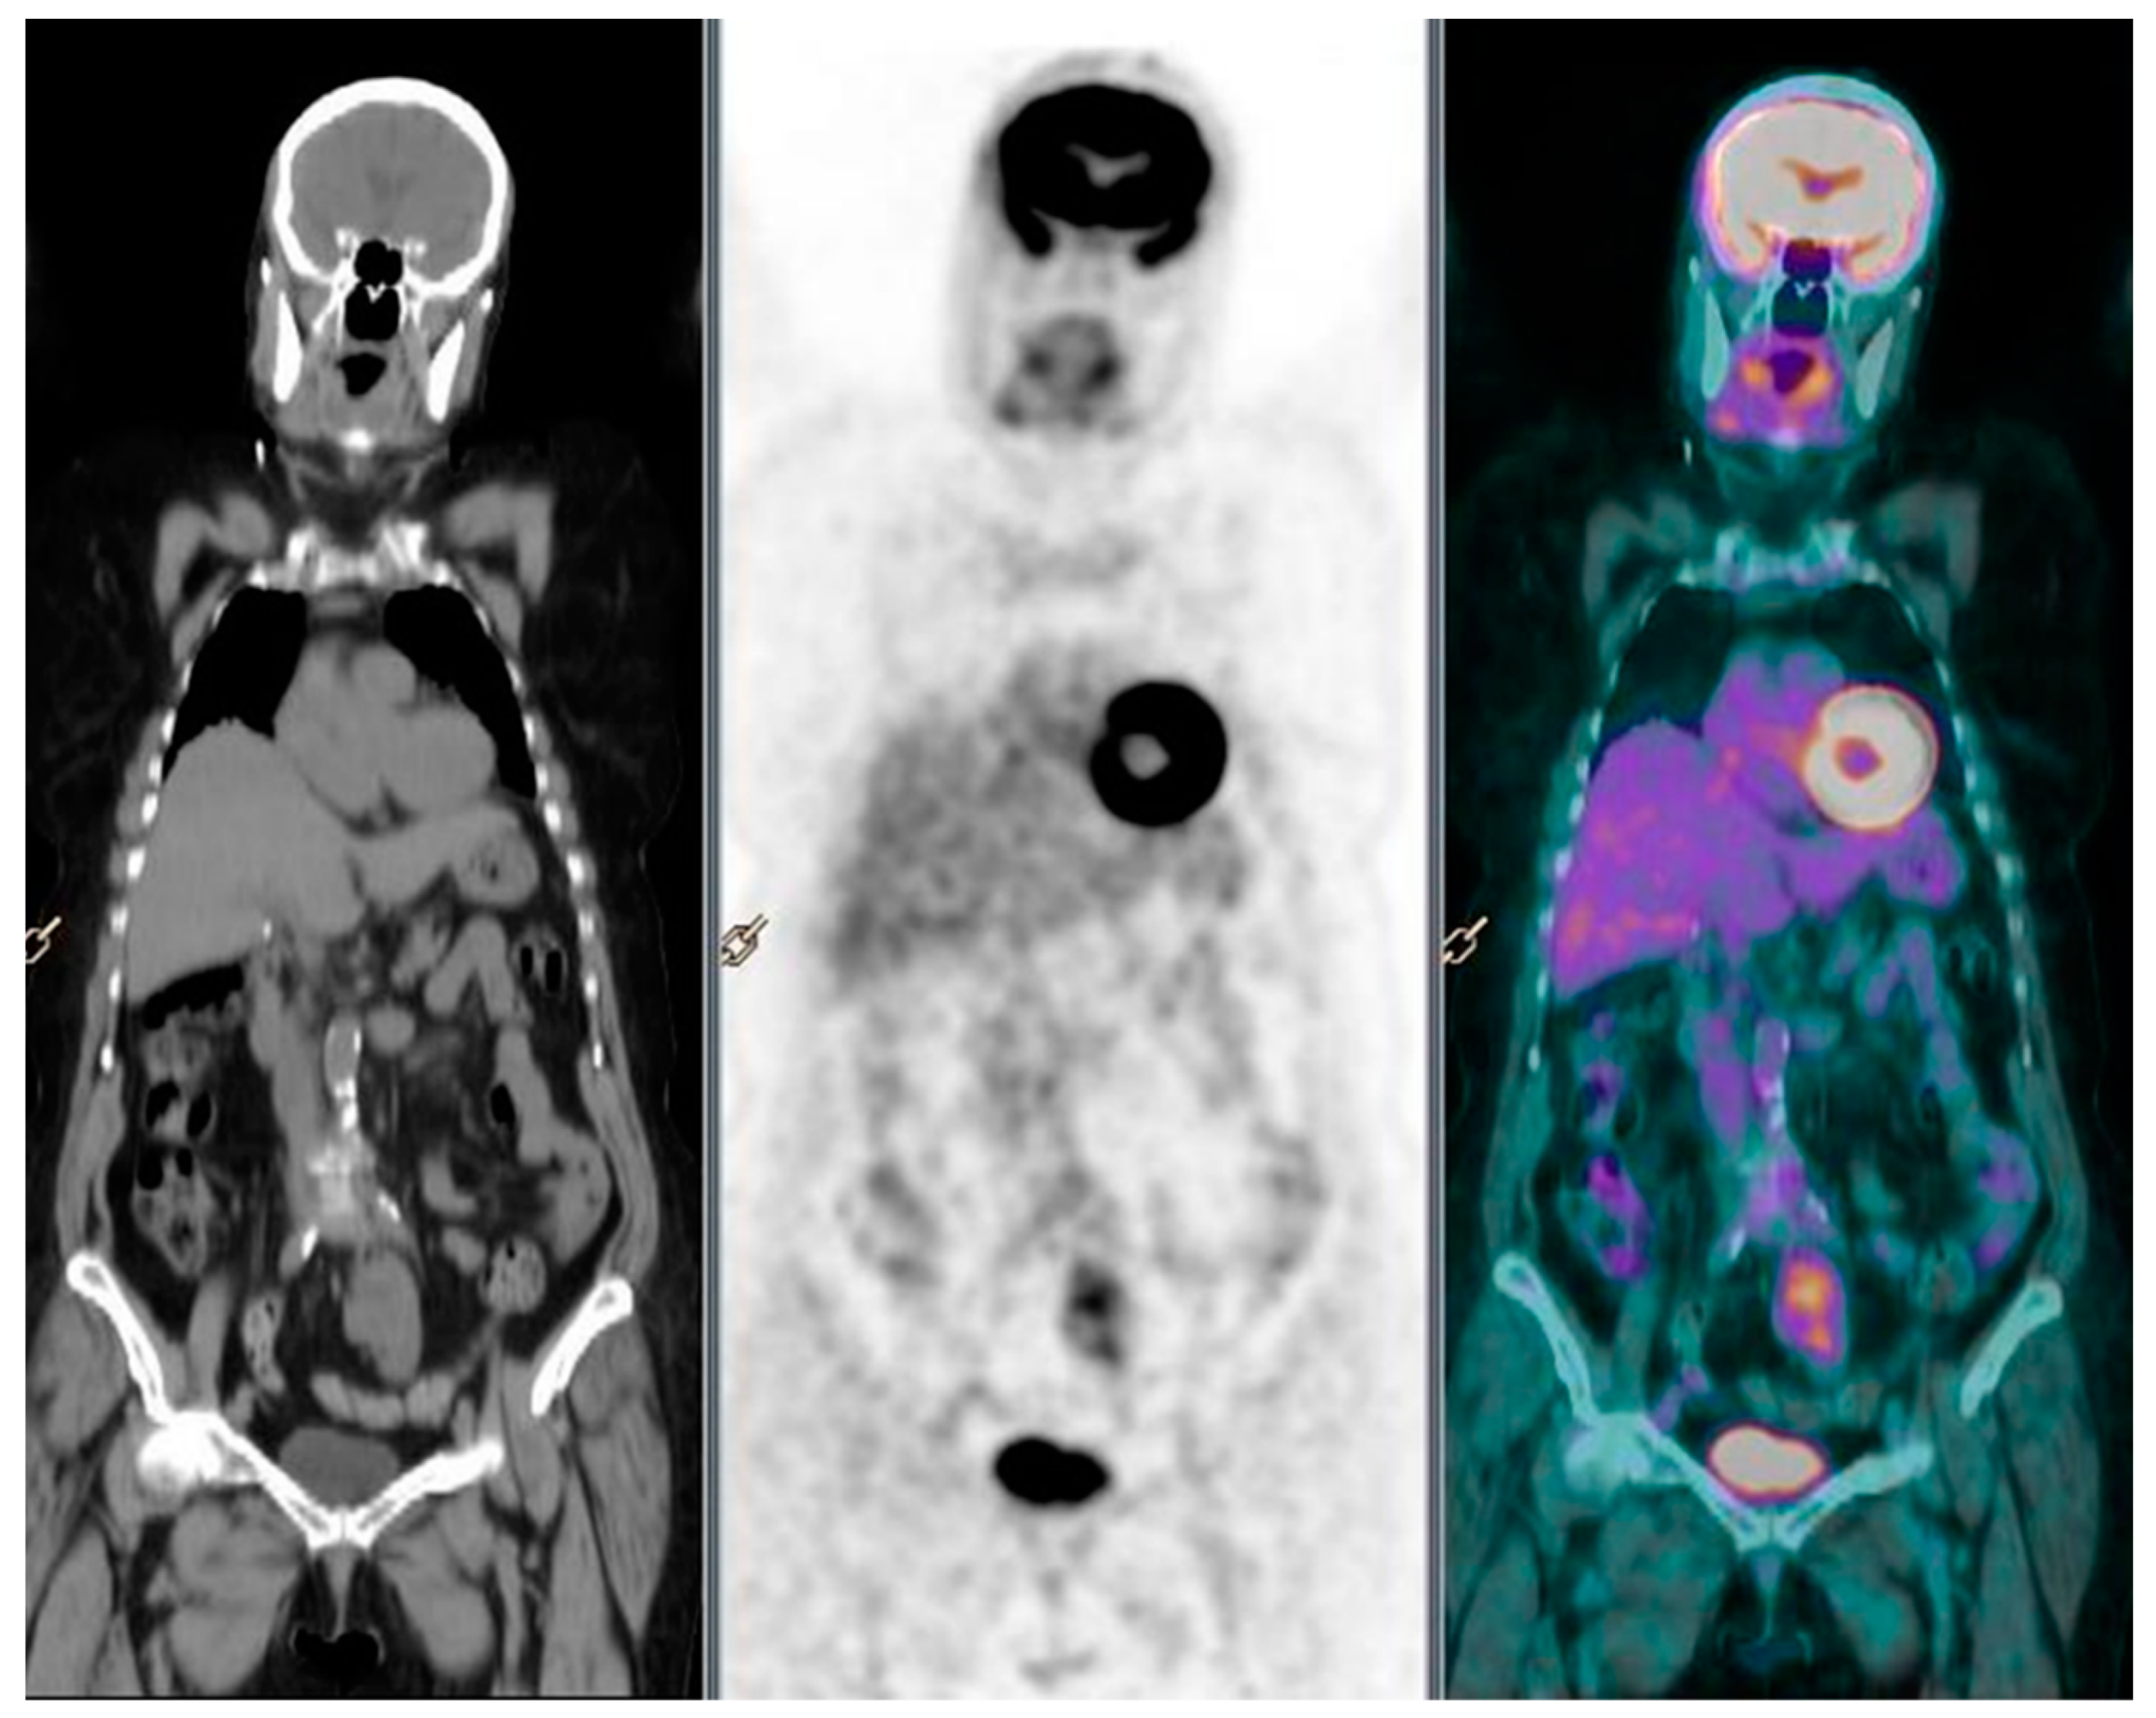

2. Case Report 1

3. Case Report 2